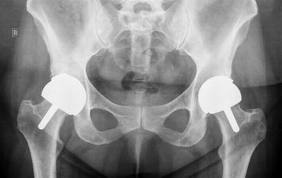

More than 800,000 joint replacement procedures are done in the United States every year, according to the American Academy of Orthopaedic Surgeons. Knee replacements are the most common, followed by hips.

Joint replacement surgery is almost always performed when arthritis has eaten away the cartilage that ordinarily cushions and protects the bones that make up joints. Surgeons will cut away what’s left of the cartilage, along with any diseased sections of bone; for shoulder and hip surgery, they’ll remove the “ball” and “socket” of the joint.

They’ll replace the removed sections with artificial pieces made of metal, plastic or ceramic materials, depending on a variety of factors, including the patient’s age, how active he or she intends to be after the surgery, and the nature of the damage in the original joint.

Doctors who specialize in joint replacement procedures say artificial joints are highly effective for a vast majority of patients. Most replacement parts are designed to last 15 to 20 years, and give patients almost the same amount of mobility as if their joints had remained healthy.